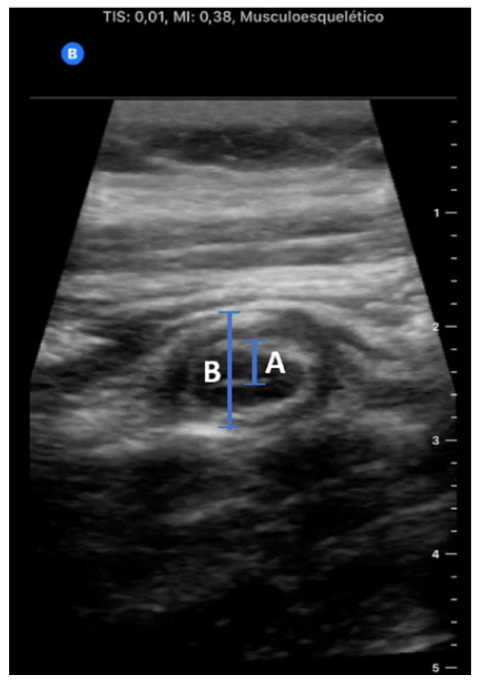

In this context, the patient was discharged home with paracetamol 1 g, three times a day, and dexketoprophen 20 mg, three times a day. However, one day later, the patient returned to the ED with abdominal pain intensification, though she maintained the same physical examination and laboratory exams. This time, an internal medicine doctor observed the patient, who performed PACE, which revealed an increased appendix diameter with noncompressible tubular structure and distorted irregular mucosa, suggestive of acute appendicitis (Fig. 1). She had no signs of ascites, nor hydronephrosis and her vaginal ultrasonography resulted without pathological alterations. Consequently, an abdominal ultrasound was performed by a radiologist, confirming the diagnosis of appendi-citis, and the patient had undergone surgery.

Figure 1: Ultrasound of the appendix, showing acute appendi-citis signs; A- Appendix wall (≈4 mm); B - Appendix diameter (≈10 mm)

The use of US in ED, performed both by radiologists and bedside clinicians, has become widespread, and consequently, it can be of great help in these cases.4 An acute appendicitis diagnosis is quite simple to be performed using ultrasonography since some easy direct signs allow its recognition: non-compressibility of the appendix, diameter > 6 mm, single wall thickness ≥ 3 mm, presence of the target sign (hypoechoic fluid-filled lumen, hyperechoic mucosa/submucosa and hypoechoic muscularis layer), the presence of an appendicolith and colour doppler and contrast-enhanced US showing hypervascularity of the wall in early stages (also called “ring of fire” edema).5 Nevertheless, considering time constraints and critical conditions of some ED patients, the US should be focused and specific to patient symptoms, as is done in the PACE approach.6

In the presented case, the protocol used was based on scanning the abdominal wall area where the patient reported more pain in search of the appendix. After this, the compressibility of the appendix was checked, and its walls and diameter were measured. According to this protocol, diagnosis can be made when a non-compressible appendix is detected with either a single wall thickness of 3 mm (or more) or an appendix diameter greater than 6 mm - all criteria were present in this case.